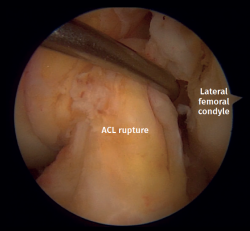

Five ACL ruptures were diagnosed in type II fractures, with 4 complete ligamentous tears (total disruption of fibers) found during arthroscopy (Figure 5). In addition, there was 1 displaced tibial eminence avulsion fracture (McKeever II)(8)(Figure 6A). PCL, LCL and MCL injuries were not found in this cohort. Likewise, neurovascular structures remained intact in all the cases studied.

Figure 5. Left knee anterior cruciate ligament (ACL) rupture. View from the anterolateral portal. Probe placed in the anteromedial portal.